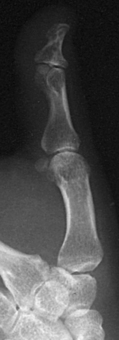

The interphalangeal (IP) articulations between the phalanges are synovial hinge type and allow only flexion and extension (Fig. 4-8). The IP joints are named by location and are differentiated as either proximal interphalangeal (PIP) or distal interphalangeal (DIP), by the digit number, and by right or left hand (e.g., the PIP articulation of the fourth digit of the left hand) (Fig. 4-9, A and B). Because the first digit has only two phalanges, the joint between the two phalanges is simply called the IP joint.

Structures shown: A lateral projection of the affected digit is shown (Figs. 4-24 through 4-27).